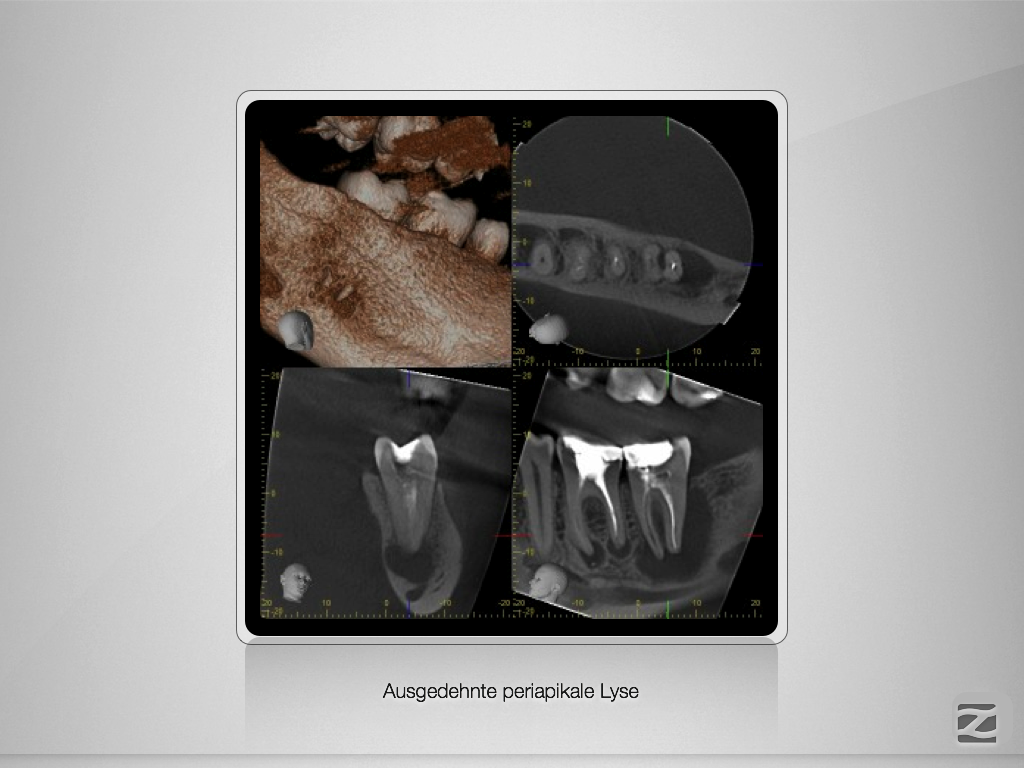

Ausgedehnte apikale Lyse